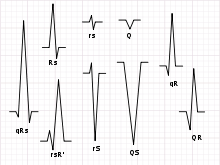

Not every QRS complex contains a Q wave, an R wave, and an S wave. By convention, any combination of these waves can be referred to as a QRS complex. However, correct interpretation of difficult ECGs requires exact labeling of the various waves. Some authors use lowercase and capital letters, depending on the relative size of each wave. For example, an Rs complex would be positively deflected, while an rS complex would be negatively deflected. If both complexes were labeled RS, it would be impossible to appreciate this distinction without viewing the actual ECG.

Looking at the precordial leads, the r wave usually progresses from showing a rS-type complex in V1 with an increasing R and a decreasing S wave when moving towards the left side. There is usually an qR-type of complex in V5 and V6 with the R-wave amplitude usually taller in V5 than in V6. It is normal to have a narrow QS and rSr' patterns in V1, and so is also the case for qRs and R patterns in V5 and V6. The transition zone is where the QRS complex changes from predominately negative to predominately positive (R/S ratio becoming >1), and this usually occurs at V3 or V4. It is normal to have the transition zone at V2 (called "early transition"), and at V5 (called "delayed transition").[6] In biomedical engineering, the maximum amplitude in the R wave is usually called "R peak amplitude", or just "R peak".[7][8] Accurate R peak detection is essential in signal processing equipment for heart rate measurement and it is the main feature used for arrhythmia detection.[9][10]